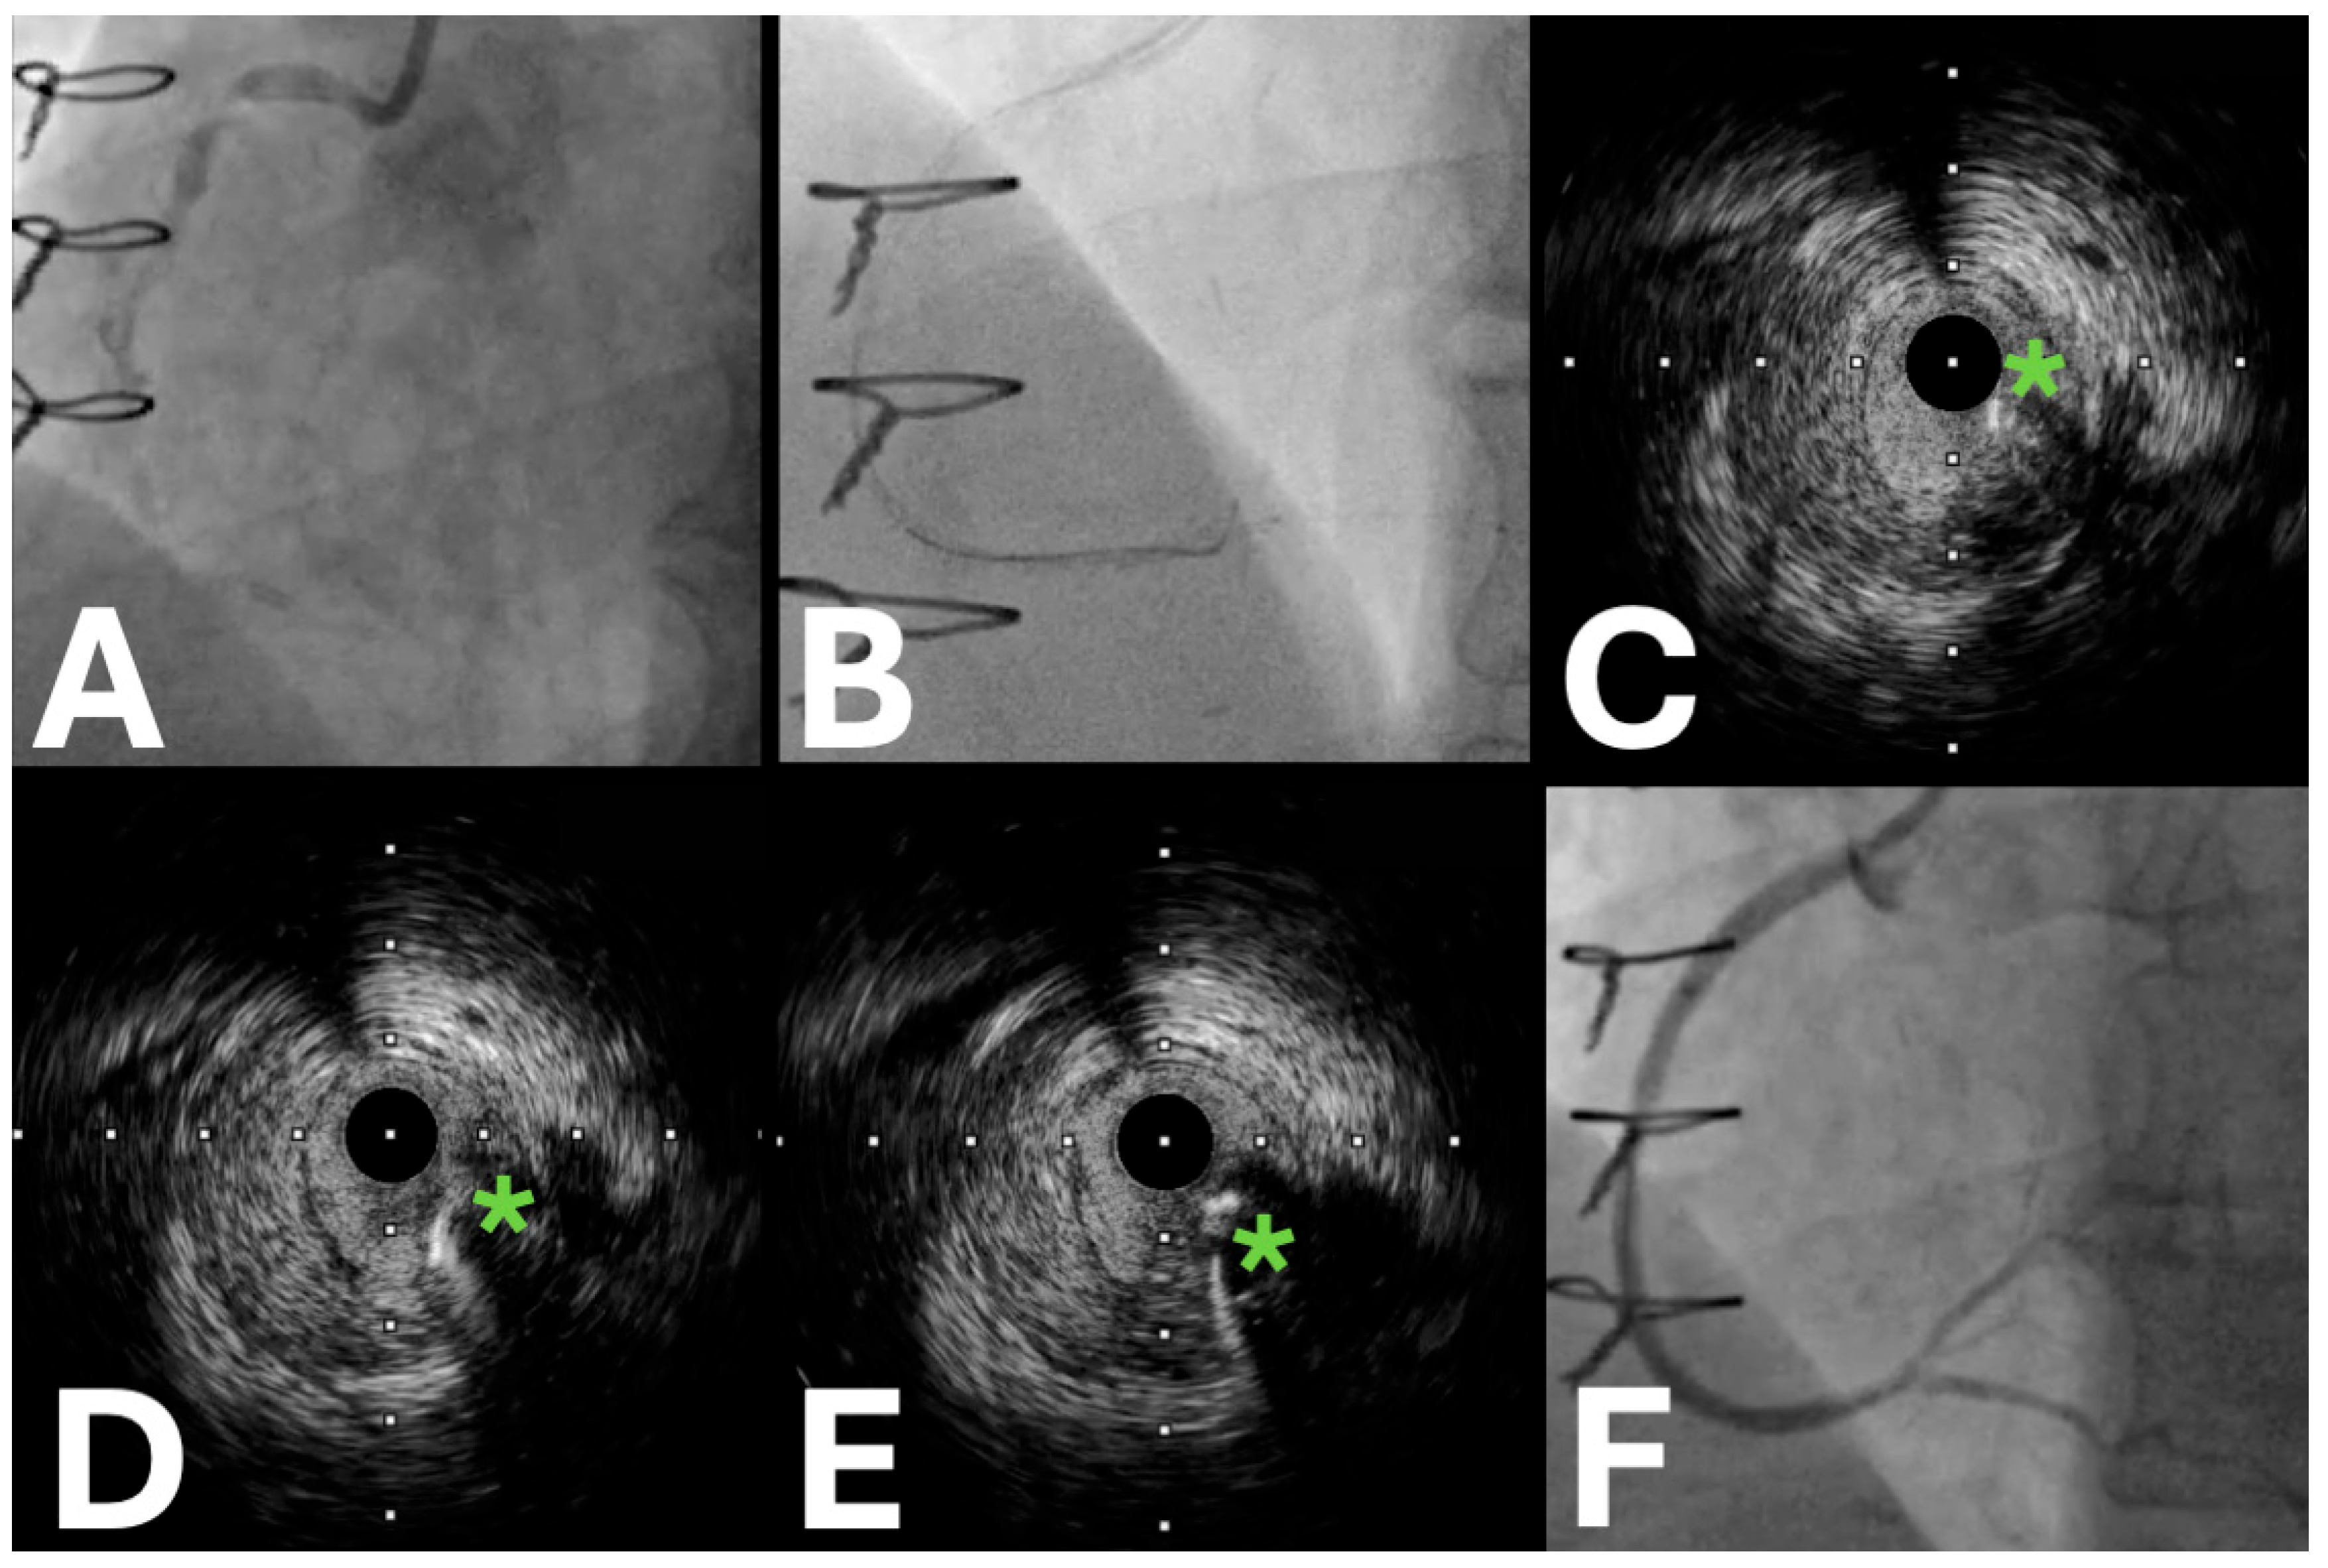

- Proximal cap puncture

- Antegrade wiring

- Antegrade dissection and re-entry

2.2. IVUS Applications in the Retrograde Approach

- Retrograde wiring

- Reverse controlled antegrade retrograde tracking